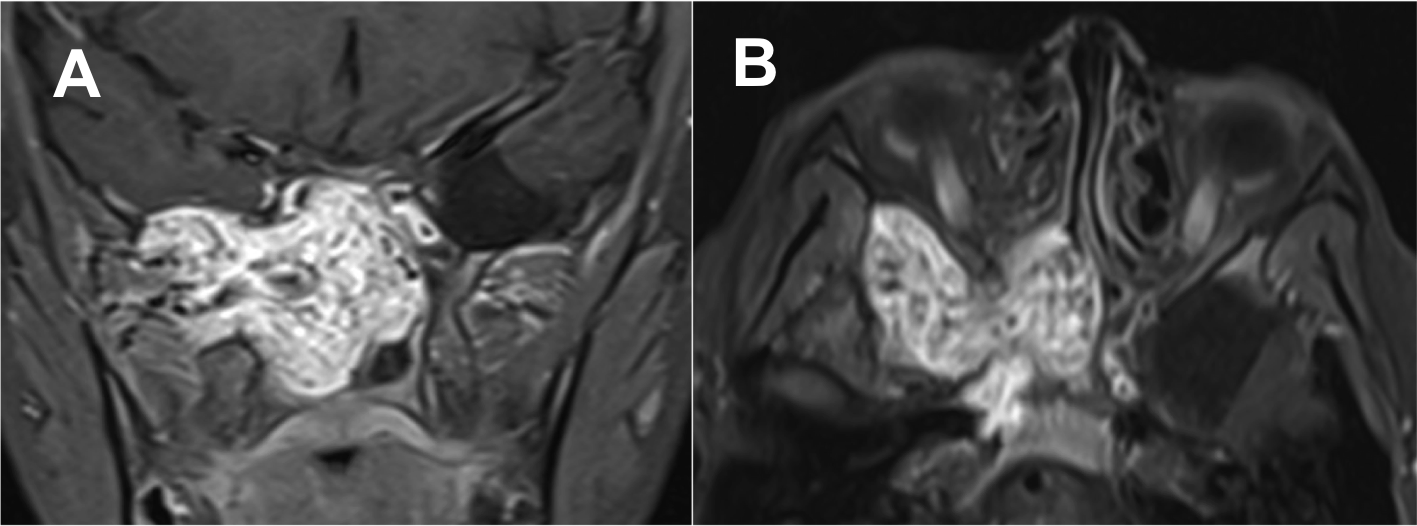

Resultados: Fueron intervenidos 8 pacientes entre los 2 y 14 años, con una edad promedio de nueve años y un seguimiento promedio de 16 meses. En el 75% se hizo una resección total del tumor. Un paciente requirió una reintervención y un paciente fue sometido a radiocirugía post-operatoria. 1 paciente falleció a pesar de múltiples intervenciones, quimioterapia y radioterapia.